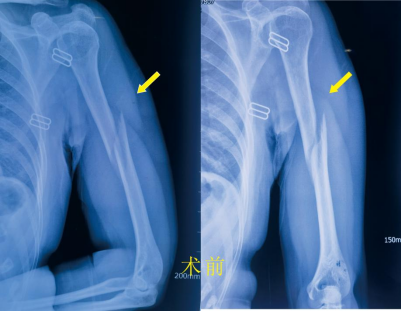

近期,家住经开区的周女士乘坐他人汽车时不幸发生车祸,左上臂撞伤,当时即感左上臂疼痛、畸形、不能活动。被120送入事故地附近医院,经X线检查提示:左肱骨中上段骨折,骨折端明显成角移位。在就诊医院,被告知需住院手术治疗。患者得知后自请转入市一医院经开区院区骨科住院治疗。

市一医院经开区院区骨科的医师接诊后详细询问病史、体格检查,明确的病情诊断,排除了胸腹等部位的内脏损伤。为了减轻患者的痛苦,帮助患者能够更快回到工作岗位,在通过CT的三维重建全面了解清楚骨折的情况后,决定给患者实行微创手术:闭合复位髓内针内固定术。 术前得到了患者和家属的积极配合,很快就将术前检查完善到位,排除手术禁忌症。经过麻醉、护理等的配合,顺利实行手术。术后给予镇痛、消肿等治疗后,1周后,患者左上臂肿胀几乎缓解了,只留下少许慢慢变淡了的瘀斑。术后12天患者拆线顺利出院。 在市一医院专家的帮扶下,市一医院经开区院区骨科以微创治疗为科室发展理念,开展了四肢骨折微创手术、脊柱的椎间孔镜手术、关节镜手术等治疗技术。不断攻克新的技术难关,提高医疗水平,提升患者就医体验,为患者提供更优质、安全、便捷医疗服务。 胡 斌 九江市第一人民医院骨三科主任 九江市第一人民医院经开区院区外二科主任 朱挺平